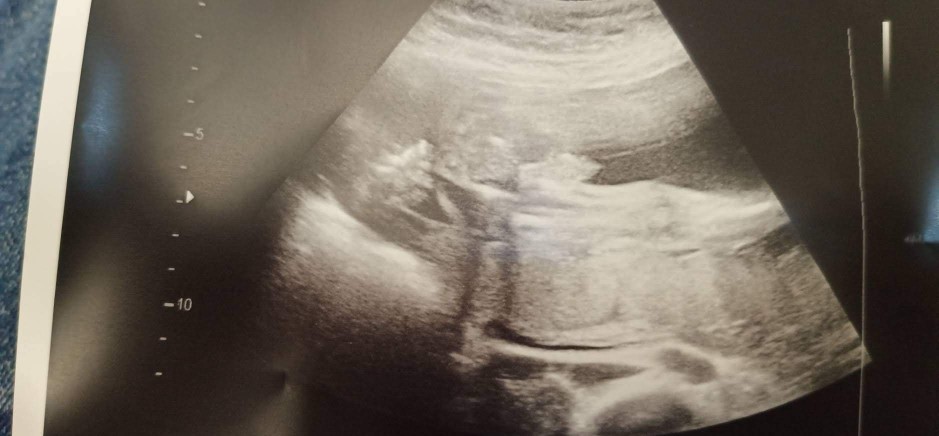

ตรงลูกศรเลยค่ะ

ชี้โด่มาเลยจ้า

ปึ๋งปั๋งมากค่ะ